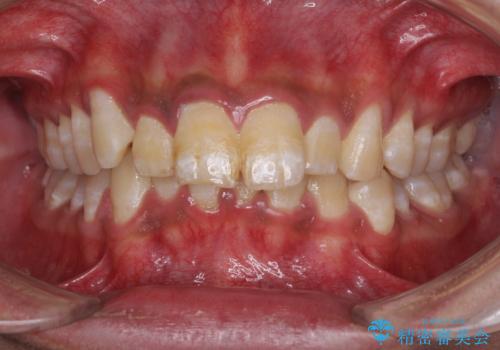

がちゃがちゃした前歯をきれいにしたい

ディープバイトと前歯のデコボコ インビザラインによる矯正治療